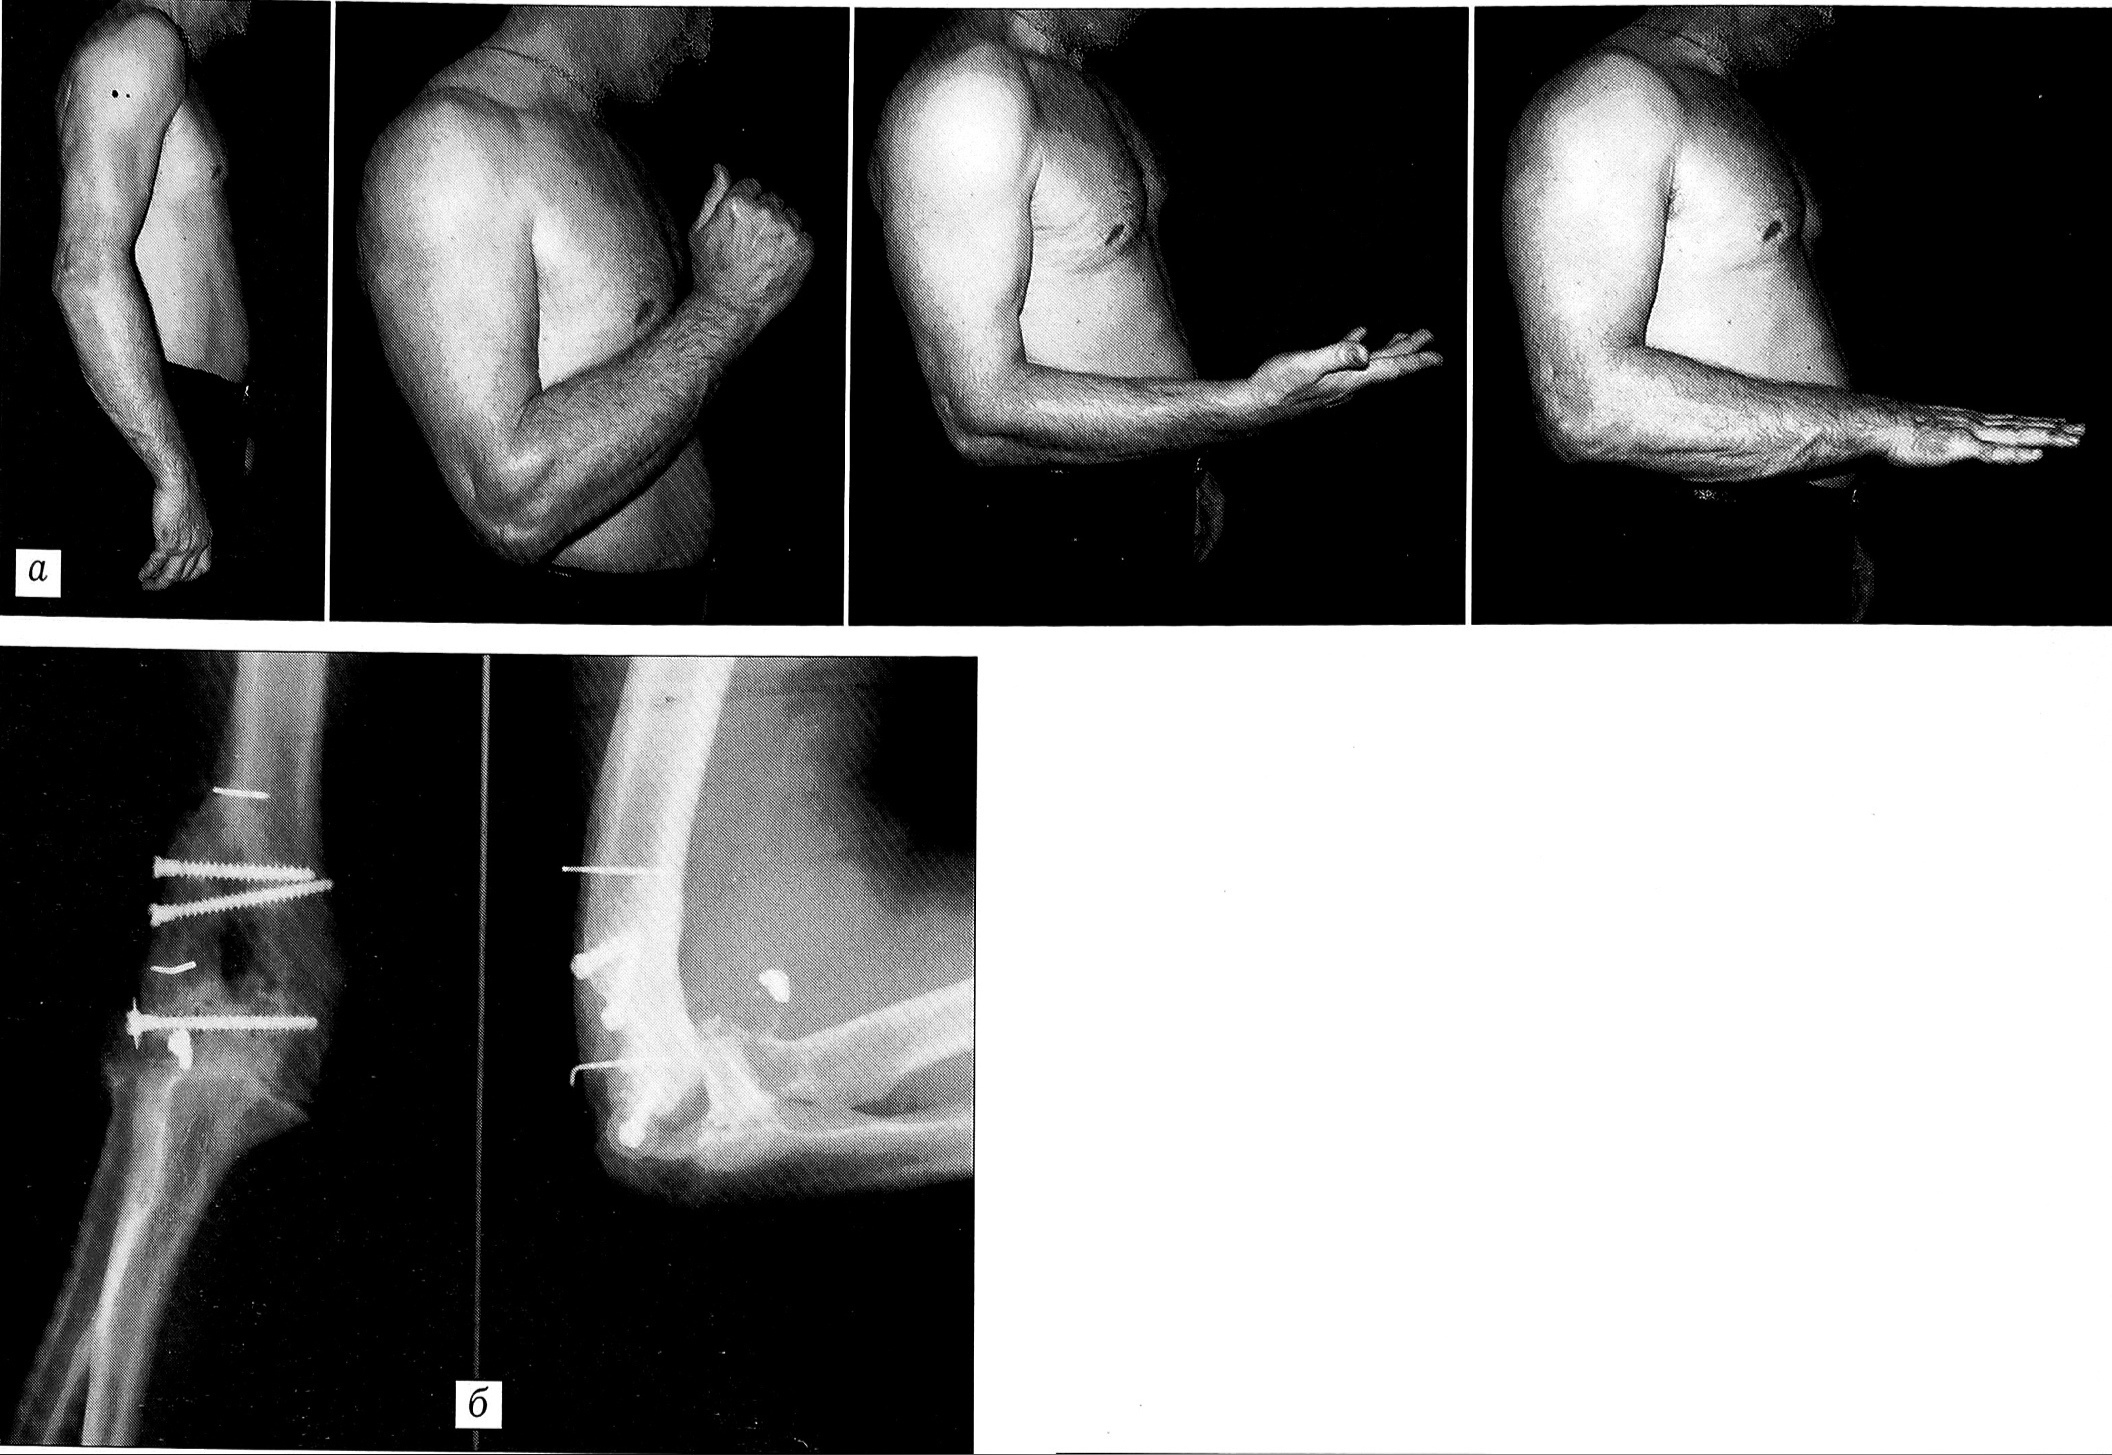

Через 8 нед на рентгенограмме определяются признаки сращения. Через 1,5 года (рис. 4) сгибание в суставе 45°, разгибание 170°, супинация и пронация в полном объеме. Восстановилась сила мышц правой верхней конечности. Сила сгибателей пальцев кисти справа 93 кг, слева 105 кг. Отжимание от пола 111 раз, отжимание на брусьях 30 раз. В настоящее время пациент работает по своей специальности (индустриальный альпинизм).

Рис. 4. Тот же больной К. через 1,5 года после операции. a — объем движений (разгибание, сгибание, супинация, пронация); б — рентгенограммы локтевого сустава.